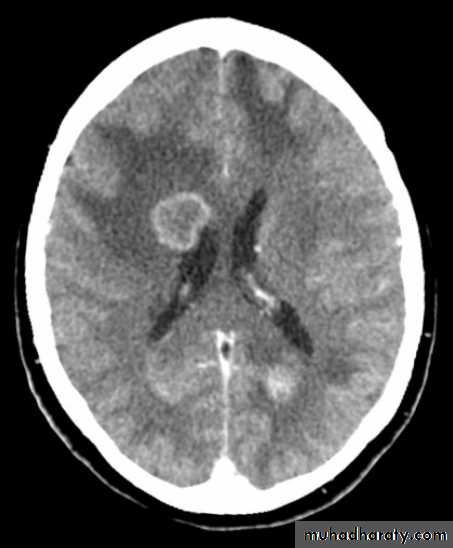

Appear as nodular single or multiple lesion hypo dense or hyper dense .

Surrounded by per focal edema

Enhanced as solid or ring pattern of enhancement .